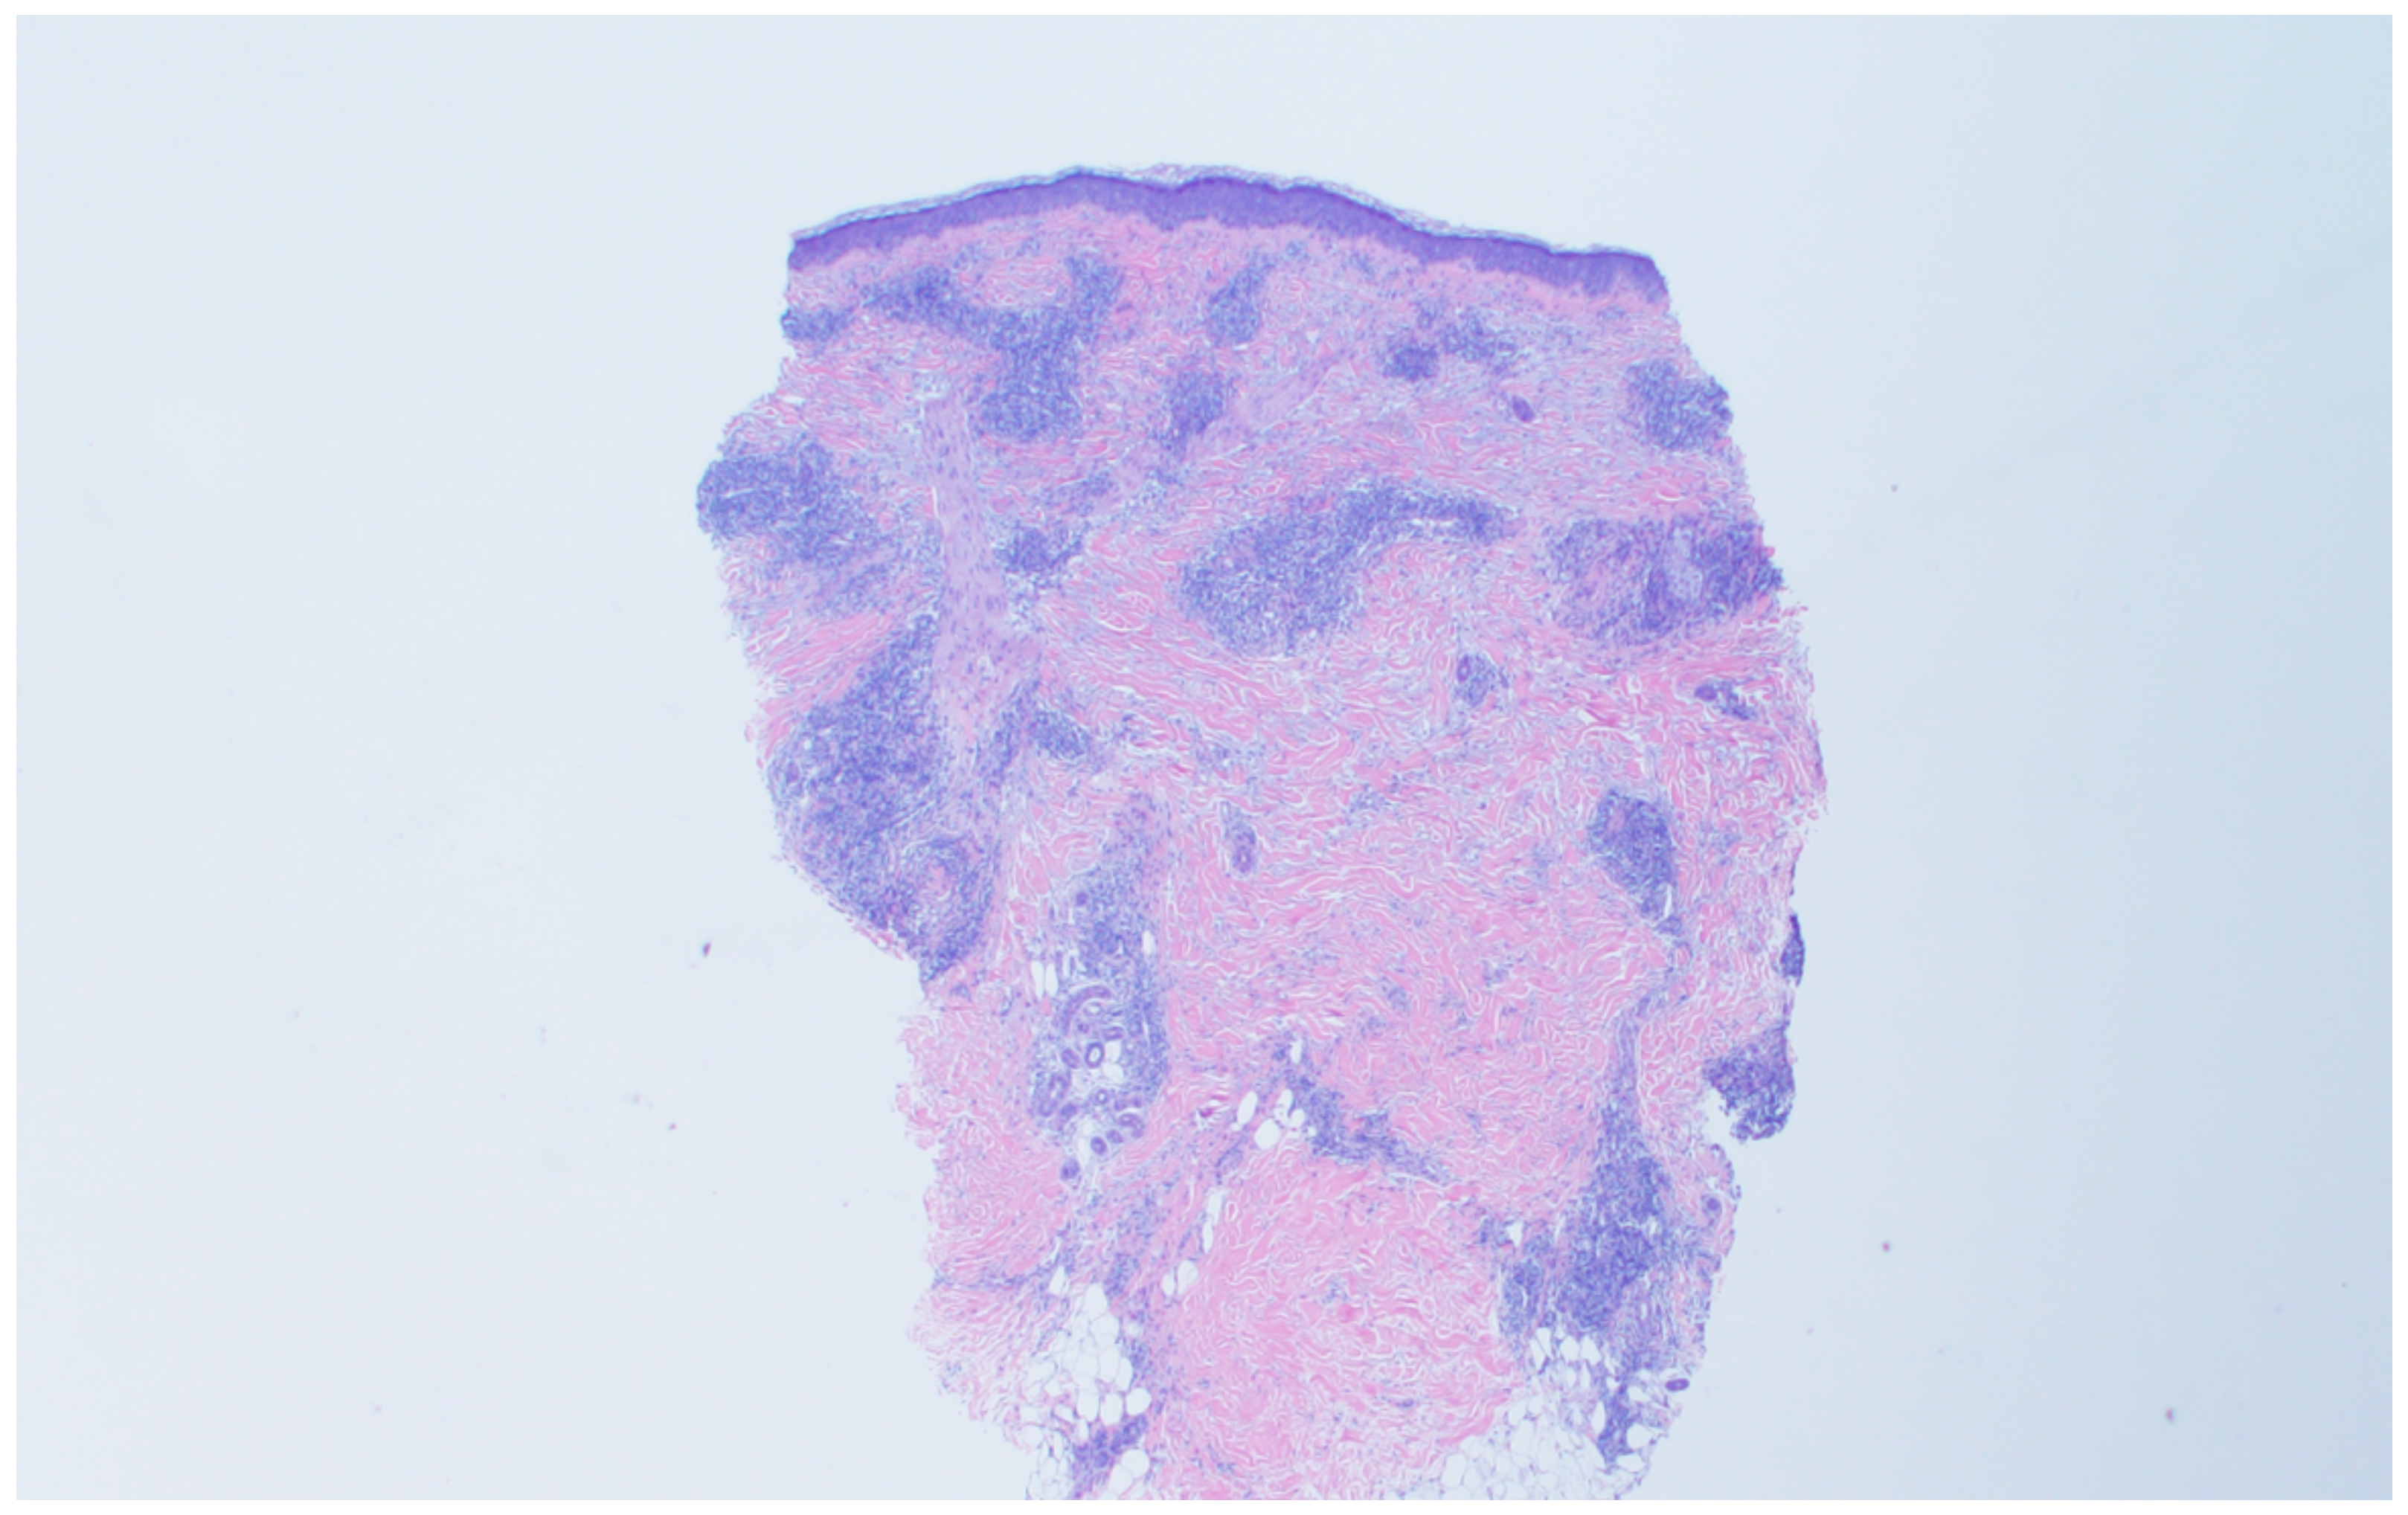

A punch biopsy was performed of the left preauricular lesion (Figure 3) at the time of presentation to the dermatologist. Histopathology of the tissue biopsy demonstrates atypical lymphoid infiltrate in the superficial and deep dermis with perivascular and adnexal involvement within the follicular epidermis. The overlying epidermis is largely uninvolved. No significant dermal mucin deposition was noted. Immunohistochemical stains highlight a CD3 positive infiltrate with a significant skew of more CD4 than CD8 presence within the follicular epithelium. Additional immunohistochemical staining is negative for CD20, BCL-6, CD10, CD21, PD1, and therefore negative for chronic T cell lymphoma, B cell lymphoma, and T cell receptor clonal rearrangements. The findings indicate a connective tissue disorder, possible tumid lupus.

Figure 3. Punch biopsy specimen from left preauricular lesion.